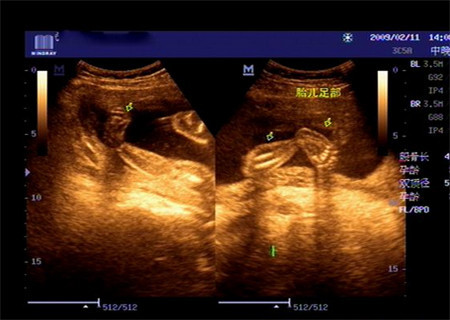

家人听到这样的消息,也非常的心痛,都劝说把胎儿给引产,可是我真的不甘心。在不顾家人的劝阻下我又分别去两个大城市做了四维检查,两家医院的医生都表示孩子是足内翻,因为足内翻会并发其他畸形,这结果也非常的不如意,家人怕承受不了最坏的结果天天都在给我做思想工作。

当宝宝出来的时候看着宝宝这样当妈的心里也不是味道,为了让宝宝尽快好起来在没出月子后就带孩子去医院看脚,医生表示孩子的左脚中度偏重,右脚轻一点,不过经过治疗—打石膏纠正和手术治疗,还是会正常的,不会影响走路,且其他方面都非常正常。